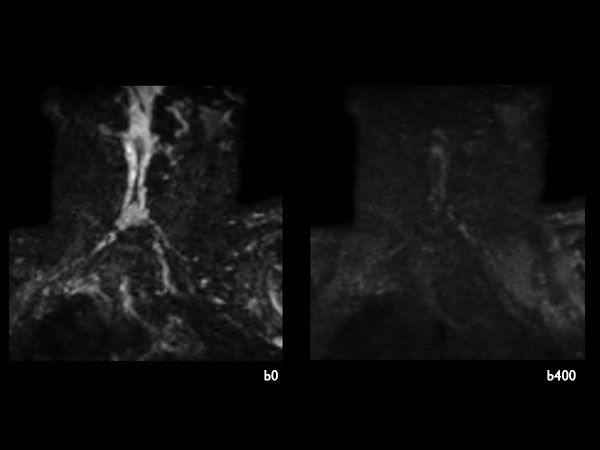

51 year-old man with poor general health and neurological disturbances. Histological examination of the surgical specimen led to the diagnosis of lipomatous ependynoma. Post surgery MRI (resected ependynoma) performed with dS HeadNeck coil with coverage till T4.